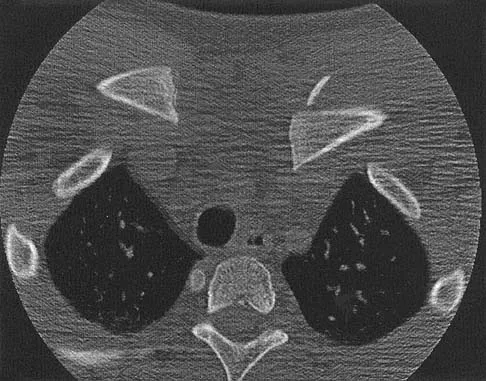

A 16-year-old girl has had hip pain for 1 year. Approximately 2 months ago she noted the development of a hard mass in the right buttock that has steadily increased in size. She now reports severe pain in the right buttock, with radiation down the leg and numbness involving the right foot and toes. A radiograph is shown in Figure 70a and an axial postcontrast T1-weighted MRI scan is shown in Figure 70b. A biopsy specimen is shown in Figure 70c. The chest CT shows multiple lung metastases. Treatment of this lesion should consist of

Explanation